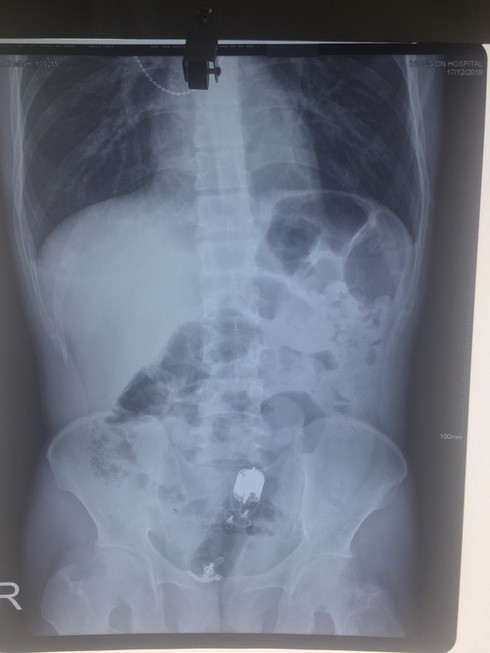

Bệnh nhân nam nhập viện trong tình trạng đau tức hậu môn. Qua X-quang và nội soi, các bác sĩ phát hiện dị vật đã chui sâu vào trong trực tràng của người đàn ông 10cm và rất khó lấy ra.

Hình ảnh chụp Xquang cho thấy dị vật chui vào sâu trong trực tràng |